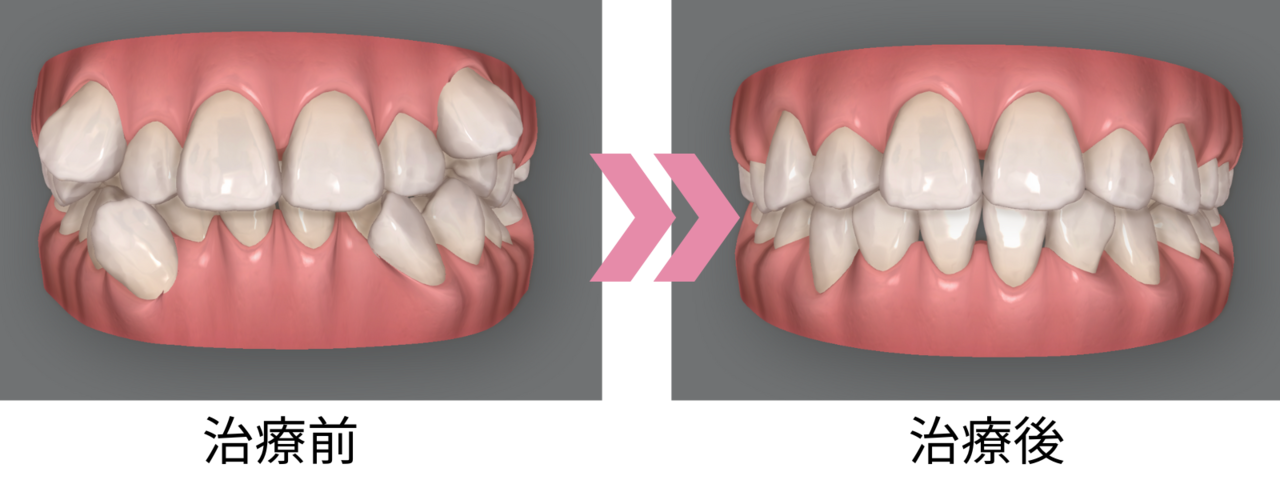

八重歯と、その隣の2番目の歯が内側に入っているガタガタ(叢生)をインビザラインで治療した症例です。

治療内容

インビザラインフル/コンプリヘンシブ

治療期間・回数

23か月・17回

治療費

総額1,166,000円(税込)

・インビザラインフル/コンプリヘンシブ:1,056,000円(税込)

・処置・管理料:110,000円(税込)

リスク・副作用

マウスピースの装着時間を守らないと、治療結果や期間に影響が出ることがあります。